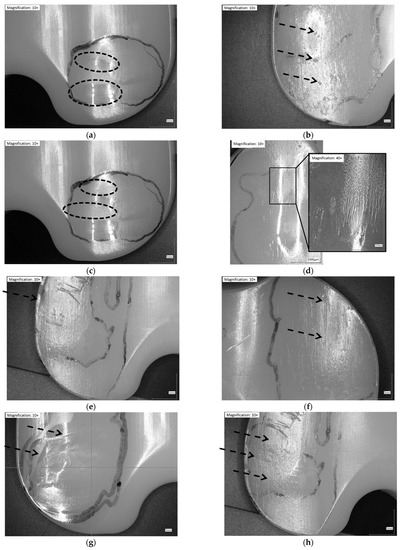

3.3. Microscopic Examination

- Pitting and TBW, the most prevalent wear patterns in the retrievals, could not be reproduced in the standard wear simulator test but could be replicated in the worst-case wear test conditions.

- Single rim-runners were detected on all the retrievals but could not be reproduced in the standard wear simulator tests; they were detected only in tibial sloped and internal rotated simulations.

| Retrievals (n = 21) | 1.9 ± 1.9 | 52.3 ± 11.7 | 29.6 ± 10.3 | 22.6 ± 12.8 | 32.7 ± 5.9 | scratching | pitting TBW | rim-runner, burnishing, abrasion |

| CoCr-ISO (n = 3) | 2.5 (1) | 23.9 ± 1.1 | 0.8 ± 0.9 | 24.6 ± 0.9 | 22.7 ± 1.5 | burnishing, abrasion, scratching | striated wear pattern | - |

| TiN-IR (n = 3) | 1.2 (1) | 27.4 ± 1.0 | 2.8 ± 0.6 | 24.6 ± 0.9 | 29.2 ± 4.9 | scratching | burnishing, abrasion | striated wear pattern,rim-runner |

| TiN-TS (n = 3) | 1.5 (1) | 34.3 ± 2.4 | 1.9 ± 0.8 | 32.4 ± 2.3 | 30.5 ± 3.0 | burnishing, abrasion, scratching | striated wear pattern, deformation | rim-runner |

| CoCr-TBW (n = 3) | 2.5 (1) | 42.1 ± 1.1 | 6.0 ± 2.0 | 36.1 ± 1.6 | 35.0 ± 1.8 | abrasion, scratching | TBW | pitting |

| Worst-case (n = 12) | 1.7 ± 0.6 (1) | 34.6 ± 6.5 | 3.6 ± 2.2 | 31.0 ± 5.3 | 32.0 ± 4.0 | abrasion, scratching | burnishing | striated wear pattern, deformation |